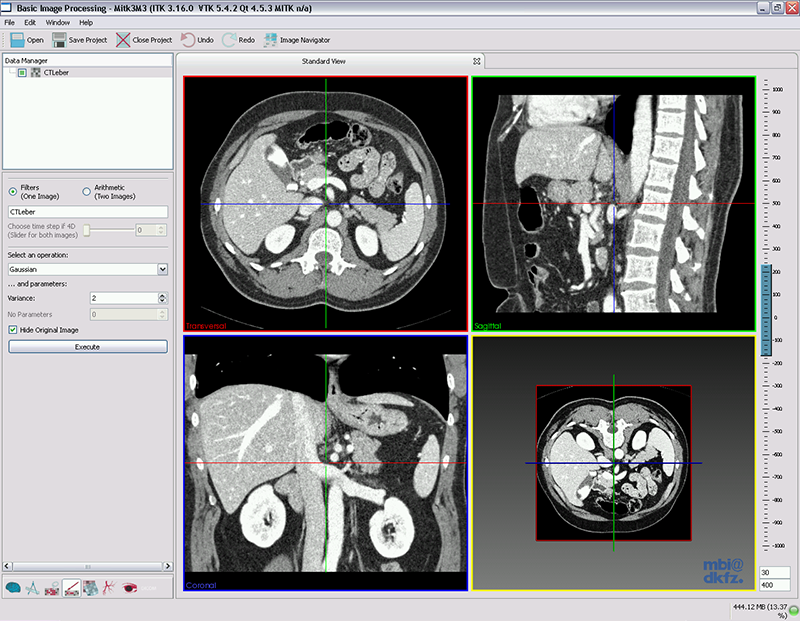

该插件是图像基本处理和增强滤波的一个简单接口。它提供了对3D和4D图像的降噪、形态学操作,边缘检测和一些图像算法,例如图像反转、降采样等。

该插件为基本的图像处理和增强滤波提供了一个接口。它提供了多种滤波操作,如降噪、形态学处理、边缘检测和其他的图像处理算法。现在支持通过MITK导入的所有3D和4D的图像,未来也会将2D图像加入进来。所有的滤波均在ITK的基础上进行封装实现的。

MITK The Basic Image Processing View

使用

使用步骤:

--加载图像

--数据管理中选择加载图像

--选择要使用的滤波器

--执行